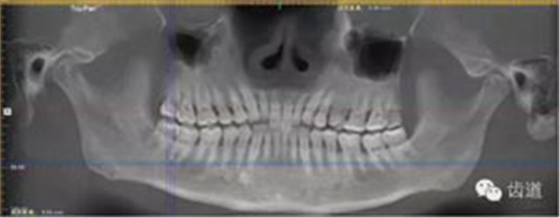

放射檢查:11,21根中三分之一至根尖三分之一處折斷。

術(shù)前放射片